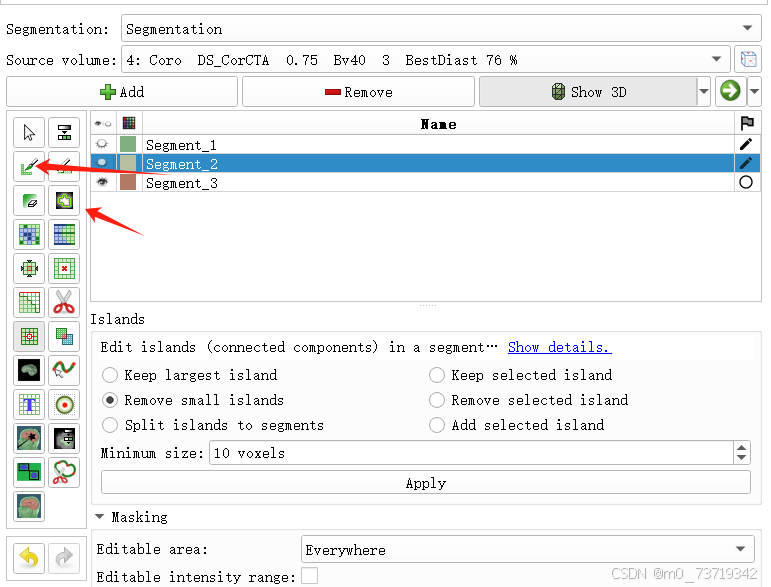

解决方法1:在标注之前先remove掉三维图像中的小噪点,显卡计算量减小,卡顿减轻